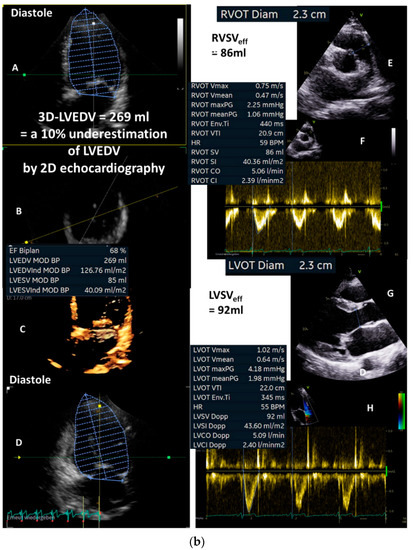

(a): Illustration of a systolic regurgitant jet phenomenon in a patient with isolated mitral regurgitation and the quantitative analysis of left ventricular volume parameters. In (A), the small vena contracta < 1 mm despite a remarkable jet area is shown. In (B), monoplane LV planimetry is shown using the apical long-axis view. In (C), the biplane LV planimetry is shown documenting a total LVSV of 90 mL. In (D), a color-coded M-Mode through the MR shows a nearly constant PISA radius. In (E), the cw regurgitant Doppler velocity is shown. LVEDV = left ventricular end diastolic volume, LVESV = left ventricular end systolic volume, LVSV = left ventricular stroke volume, LVSVtot = total LVSV, and LVEF = left ventricular ejection fraction. (b): Illustration to assess quantitatively effective LVSV and RVSV by pw Doppler echocardiography as well as regurgitant volume by 2D PISA method to analyze severity of mitral regurgitation (MR): in (A), the parasternal long-axis to document LVOT diameter during systole is shown; in (B), the measurements of LVSVeff by pw Doppler spectrum at the level of the LVOT is shown; in (C), the parasternal and subcostal short-axis views are shown to document RVOT diameter during systole; in (D), the measurements of RVSVeff by pw Doppler spectrum at the level of the RVOT is shown. The estimation of RegVolMR by 2D PISA is demonstrated by delineation of the 2D-PISA radius and the velocity time integral of the retrograde transmitral velocity during systole (E,F). LVSV = left ventricular stroke volume, LVEF = left ventricular ejection fraction, LVSVeff = effective LVSV, RegVol = transmitral regurgitant volume, LVOT = left ventricular outflow tract, RVOT = right ventricular outflow tract.

Figure 4.

At this point in the examination, the findings should be checked for hemodynamic plausibility. Calculating the minimum effective LVSV to enable a required effective CO and CI at a heart rate of 63/min (corresponding to values of approximately CO = 4 L/min; CI = 2.2 L/min m2: 4000 mL/min/63/min = 63 mL) facilitates the interpretation. Thus, the maximum possible RegVolMR to be above shock limit is (90 mL − 63 mL = 27 mL), which corresponds to a RF of 30%.

Next, the effective LVSV should be quantified by Doppler echocardiography (Figure 4b(A,B)—pw-Doppler LVOT, Figure 4b(C,D)—pw-Doppler RVOT), yielding approximately 75 mL (Figure 4b(E,F)). Thus, RegVolMR was 15 mL in this case. RegVolMR can additionally be checked by 2D PISA method if there are no methodological limitations to the use of 2D PISA method (Figure 4a(D)—color-coded M-Mode—MR, Figure 4a(E)—cw-Doppler—MR, Figure 4b(E,F)—2D PISA method). Thus, RFMR was less than 20% in this case. In conclusion, secondary alterations, e.g., increased E/e’ ratio and/or increased systolic pulmonary arterial pressure, associated with relevant MR, should be considered to exclude high-grade MR.